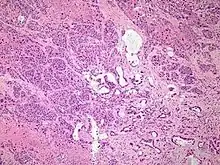

| Micrograph of an adenosquamous carcinoma of the lung. The adeno- or glandular component is on the left of the image and the squamous component on the right of the image. H&E stain. | |

Light microscopy shows a combination of gland-like cells and squamous epithelial cells.[4] On immunohistochemistry, it is typically positive for CK5/6, CK7 and p63, and negative for CK20, p16 and p53. On genetic testing, KRAS and p53 are typically altered.[4]